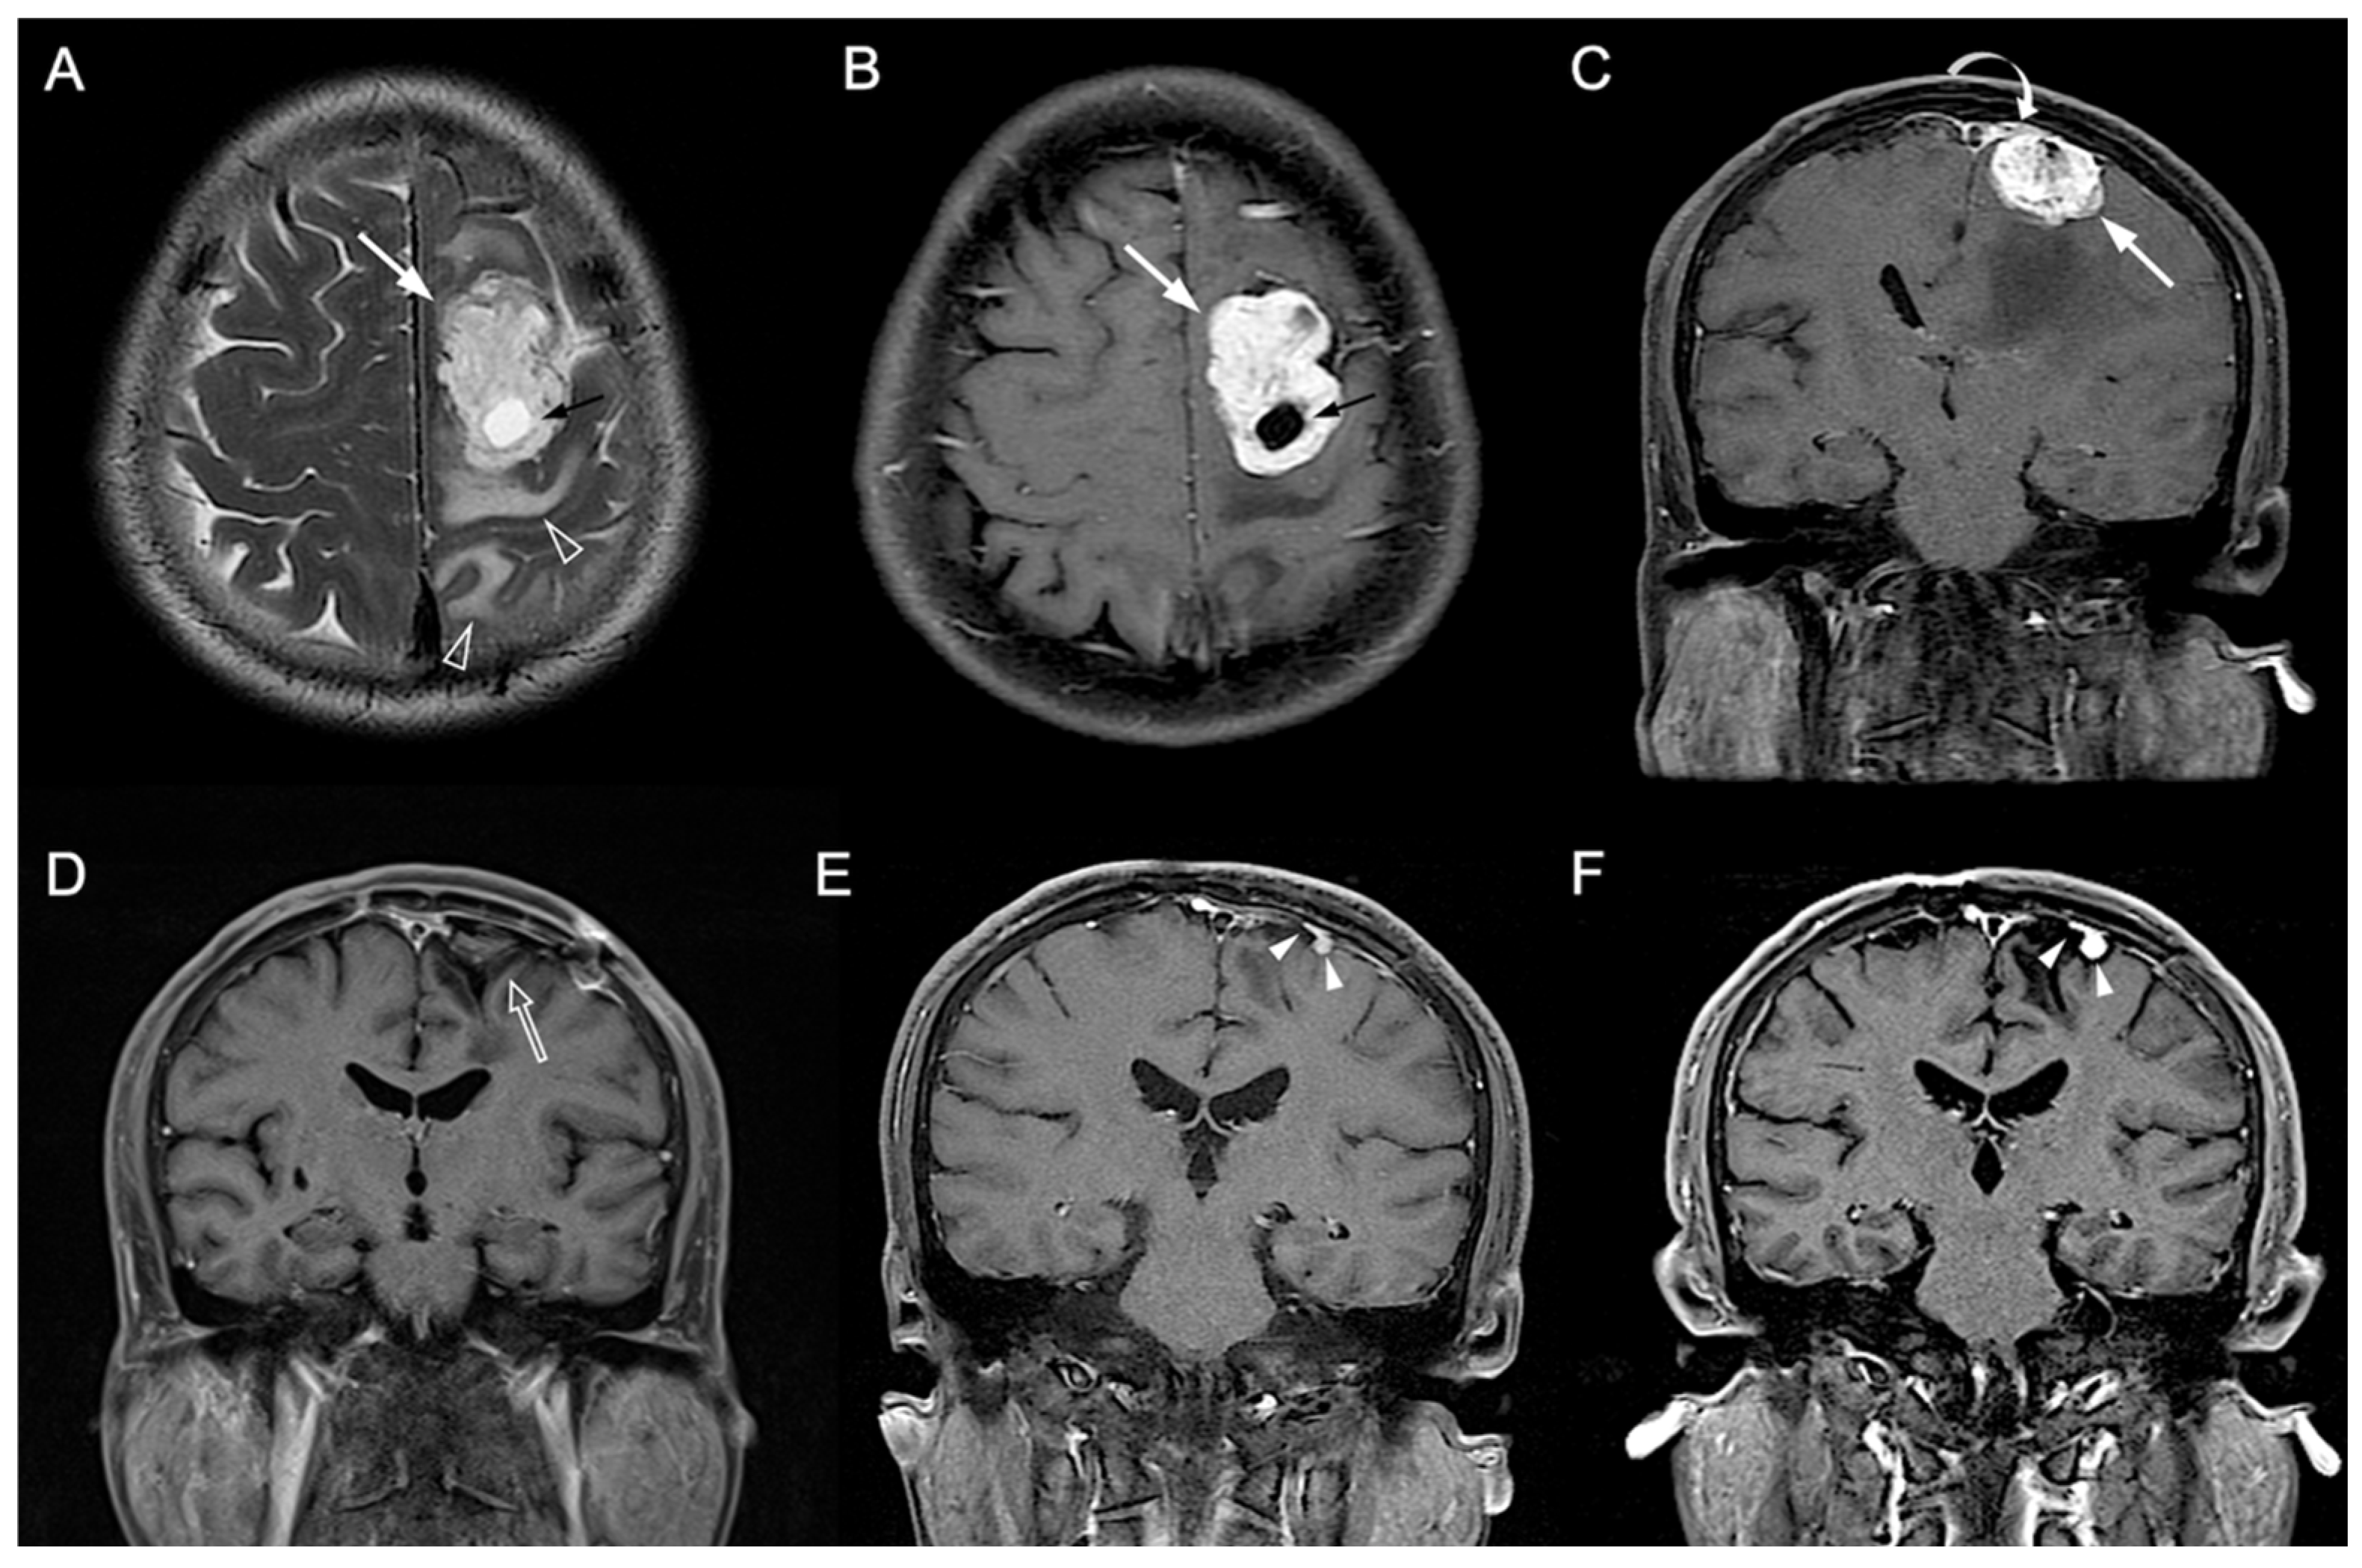

3.1. Clinical and Imaging Findings